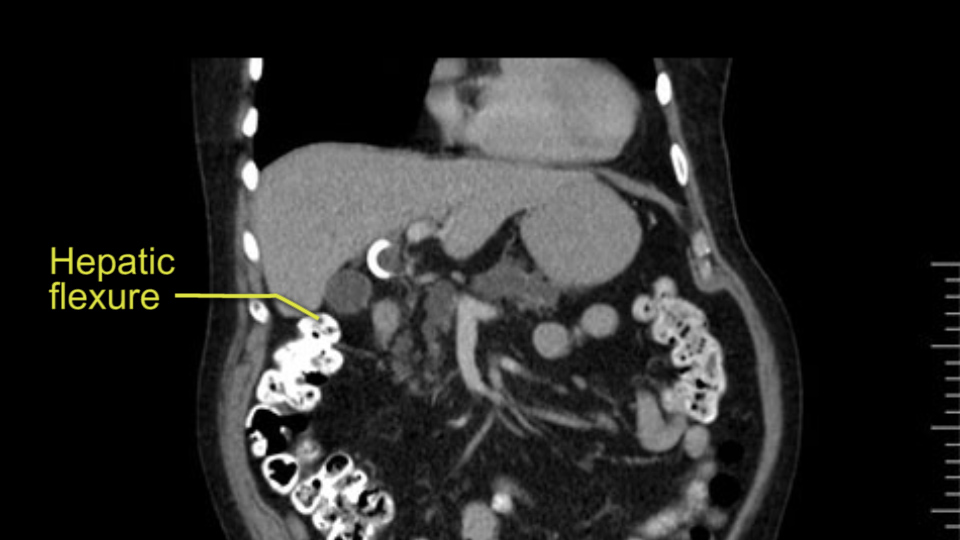

The other thing I look at is the gastroepeiploic arcade- which is this thing here- which is where the gastroepeiploic vein joins the portal vein. I call it the gateway to the neck of the pancreas because you pretty much have to divide it to get to the neck. The middle colic vein usually drains either into it or nearby. I think we’re seeing it here. Again,that can be divided and I usually divide those two and it helps me get under the neck. Again, there’s no issues here with the tumor so it’s nice from that perspective. If I was concerned about the vein, which I’m not here, I would go to the coronal view. It’s a nice way to look at the vein on just a couple of cuts and you can see a beautiful view of it here. There’s the portal vein, there’s the head of the pancreas. There’s the tumor. It’s a little closer here than it looks on the other one. I doubt it’s involved. If it’s touching, it may not be invading it but even if it was, it's a short segment. Anyways, there’s the SMV there’s the splenic vein, and everything looks good. You can see the stent. I ignore the stent. It’s the most dramatic looking thing in the picture but it’s actually the least important.

In planning for my further steps, the first key that I find, first do a gentle mobilization of the hepatic flexure of colon completely away because that’s going to help me do a good wide Kocher maneuver. Why do I slow down? Because there are small tributaries and small blood vessels which communicate between the transverse mesocolon and the head of the pancreas and you also have the loop of Henle all the blood vessels which drain into the superior mesenteric vein just as it gets underneath the neck of the pancreas.

The initial hepatic flexure mobilization and the Kocher procedure is then going to enable me to understand the uncinate process of this patient, which should not be a problem, again. But the initial pictures had shown a degree of touching. I would not even say involvement or abutment; a degree of touching with the superior mesenteric vein. So that would give me an early chance to assess how the superior mesenteric vein is in this patient. So this would be the initial slowing down moment.